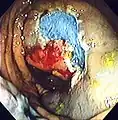

An advantage of colonoscopy over X-ray imaging or other less invasive tests is the ability to perform therapeutic interventions during the test. A polyp is a growth of excess of tissue that can develop into cancer. If a polyp is found, for example, it can be removed by one of several techniques. A snare device can be placed around a polyp for removal. Even if the polyp is flat on the surface it can often be removed. For example, the following shows a polyp removed in stages:

Polyp is identified.

Polyp is identified. A sterile solution is injected under the polyp to lift it away from deeper tissues.

A sterile solution is injected under the polyp to lift it away from deeper tissues. A portion of the polyp is now removed.

A portion of the polyp is now removed. The polyp is fully removed.

The polyp is fully removed.